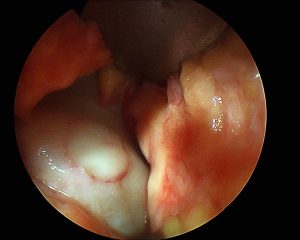

• Das Transplantat wird aus einem relative entlasteten Gelenkareal, z.B. dem lateralen oder medialen Patellagleitlager bzw.Trochlearand, der Notch, oder den dorsalen Kondylen gewonnen. Für die Entnahme aus den dorsalen Kondylen benötigt man eine Umlagerung und einen Zugang nach Trickey, erhält aber dabei meist sehr gute Knorpel-Knochenzylinder (passende Konvexität)

• Entnahme des oder der Defektzylinder (weiß) Donor wichtig im korrekten Winkel entnehmen!

• Gewinnung des Zylinders:

• Entnahme des oder der Zylinder (blau) Recipience